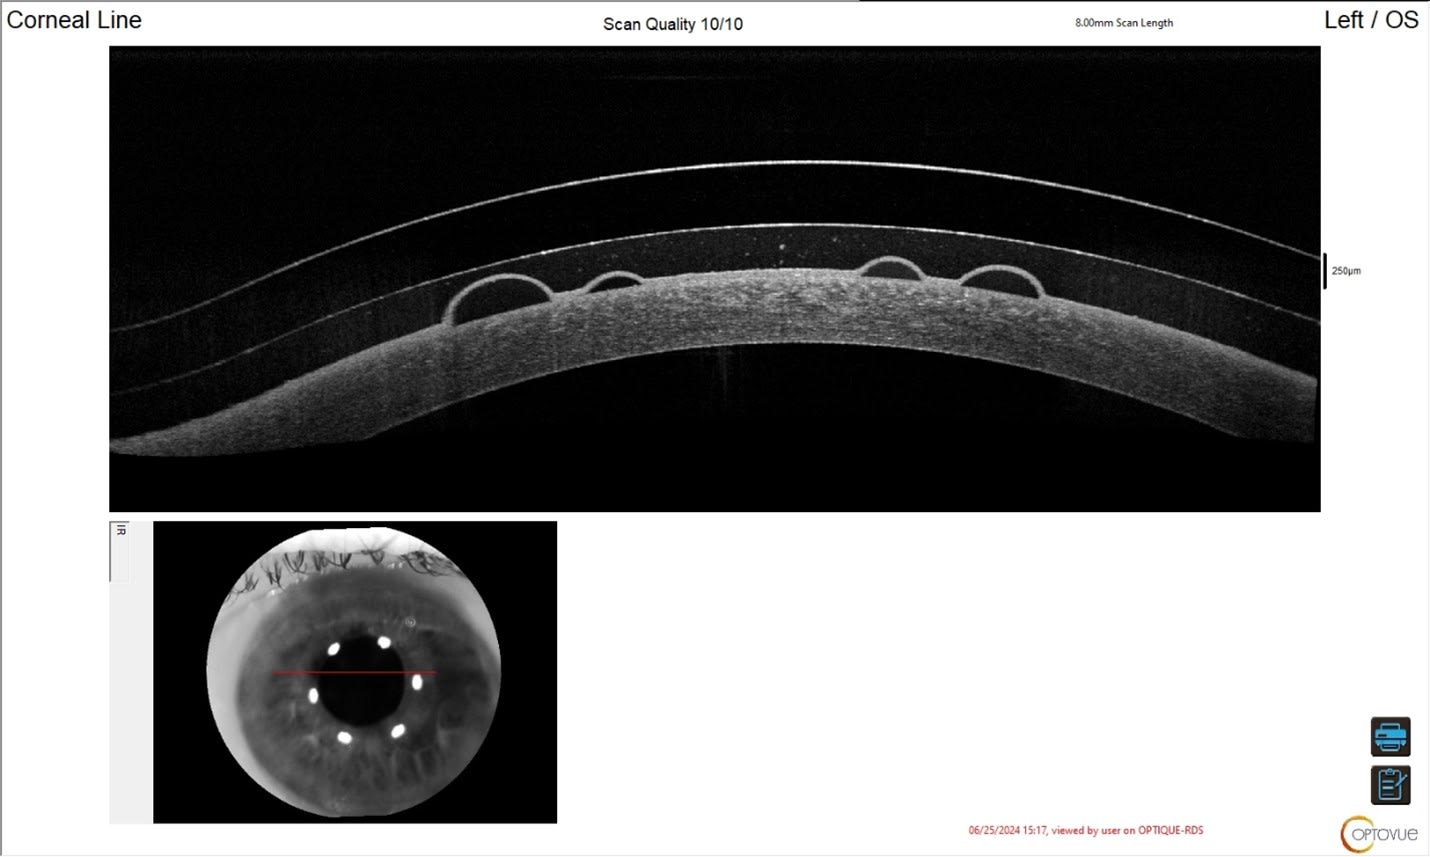

At dispense, AL’s vision was 20/20+2 OS. The anterior segment OCTs are shown below (Figures 2 through 6). We imaged scleral prosthetic lenses centrally and in four principal meridians at the haptics to ensure an optimal fit.

At the two-week visit, we noted that the limbal zone was tight (Figure 7), either due to forceful insertion (which creates a suction effect and pulls the lens onto the limbus) or standard settling of a prosthetic with spongy conjunctival tissue. We opted to educate the patient about gentle insertion technique and increased the optical zone diameter to allow for greater limbal clearance.

Lenses were dispensed with a larger optical zone diameter to preserve their overall diameter and to allow for greater limbal clearance nasally and temporally—where the cornea is widest after settling onto the eye (Figure 8).